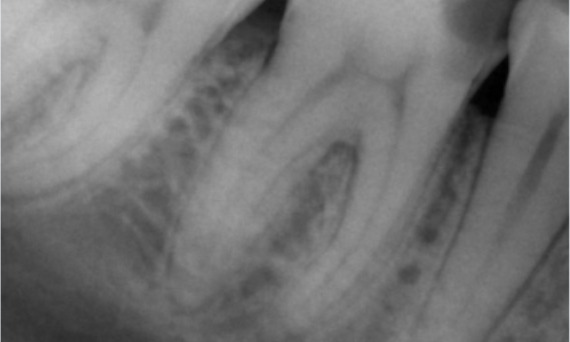

Vorher: Bei der Untersuchung wurde eine Karies-Läsion am unteren rechten ersten Molaren festgestellt. Bei der röntgenologischen Untersuchung zeigte sich die Nähe der Läsion zum Pulpahorn. Zusammen mit den Hauptbeschwerden wurde die endgültige Diagnose einer chronischen irreversiblen Pulpitis gestellt.

Nachher: Die Zugangskavität wurde so konservativ wie möglich gestaltet. Da es sich um einen jungen Patienten handelte, war TruNatomy das System der Wahl. Wir mussten das Dentin so weit wie möglich erhalten, um die Fähigkeit des Zahns zur Bewältigung der okklusalen Belastung und die Langlebigkeit der endgültigen Restauration zu erhöhen.

Kairo, Ägypten